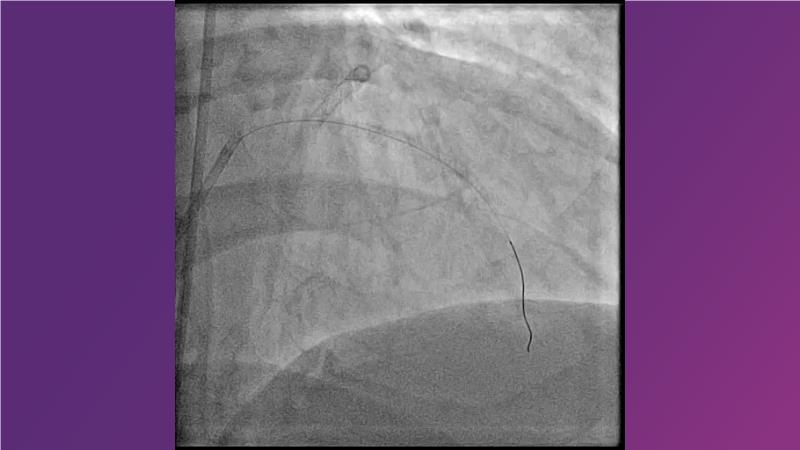

Cracking calcium: best practices to integrate intravascular lithotripsy into your calcium management algorithm

With this session, keep up to date on the evidence, trials and outcome data for intravascular lithotripsy in severely calcified lesions. Learn how to use this technique in real-world patients and understand its role in the treatment algorithm for severely calcified coronary lesions.

- To know the evidence, trials and outcome data for intravascular lithotripsy in severely calcified lesions